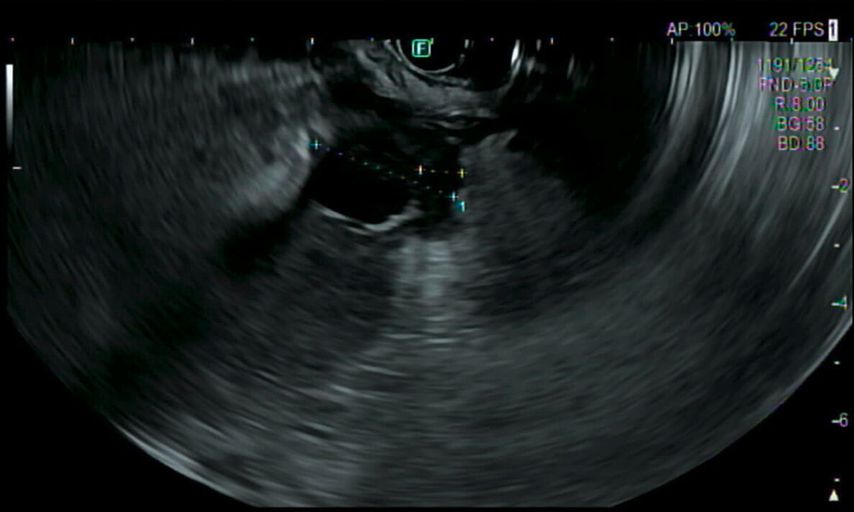

In der durchgeführten Computertomografie des Abdomens (Abb.1) zeigt sich der Verdacht auf einen hohen Ileus mit prall sekretgefülltem, distendiertem Magen (25cm kraniokaudal). Weiters stellt sich die Magenwand auf bis zu 17mm verdickt dar – mit intramuralen Lufteinschlüssen, insbesondere entlang der großen Kurvatur. Eine Ausgangsstenose im gastroduodenalen Übergang wird suspiziert. Rasch wird eine nasogastrale Sonde eingebracht, die trotz korrekter Lage kein Sekret fördert.

Im Rahmen der Narkose wird eine Sonografie des Abdomens ergänzt, in der sich nun der Verdacht bestätigt, dass die große Fluidokollektion nicht im Magen, sondern intramural in der ventralen Magenwand liegt.